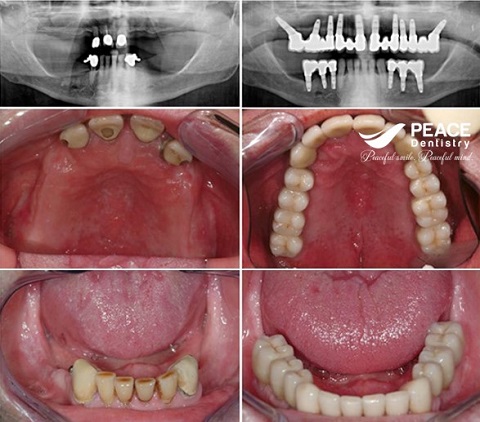

(Missing all teeth on both jaw, traditional implant for upper jaw and all on 4 for lower jaw)